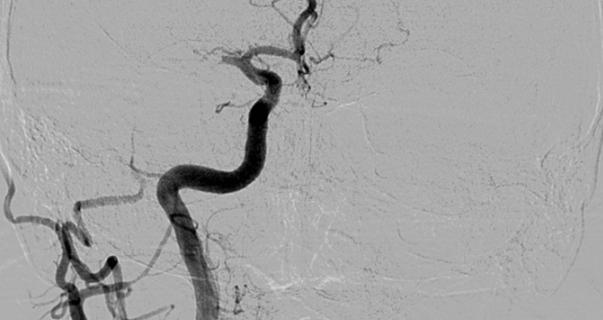

Se realiza una serie a través del catéter balón que demuestra una recanalización parcial del segmento M1 proximal con apertura de arterias lenticuloestriadas y persistencia oclusión de segmento M1 distal de ACM derecha (imagen 3). Se decide cambiar de estrategia y usar la técnica SAVE con Catalyst 5, Trevo Pro 18, Asahi Chikai 0.014’’ y Catch 6 x 30 mm.

La técnica SAVE consiste en combinar stentriever (colocándolo con el trombo en su tercio proximal) y un catéter de aspiración (en contacto con la porción proximal del trombo) y realizar el pase actuando como una unidad, ofreciendo una captura distal (stentreiver) y proximal del coágulo con el catéter de aspiración (imagen 4). Se retiran simultáneamente bajo aspiración con bomba y manual a través del catéter balón.